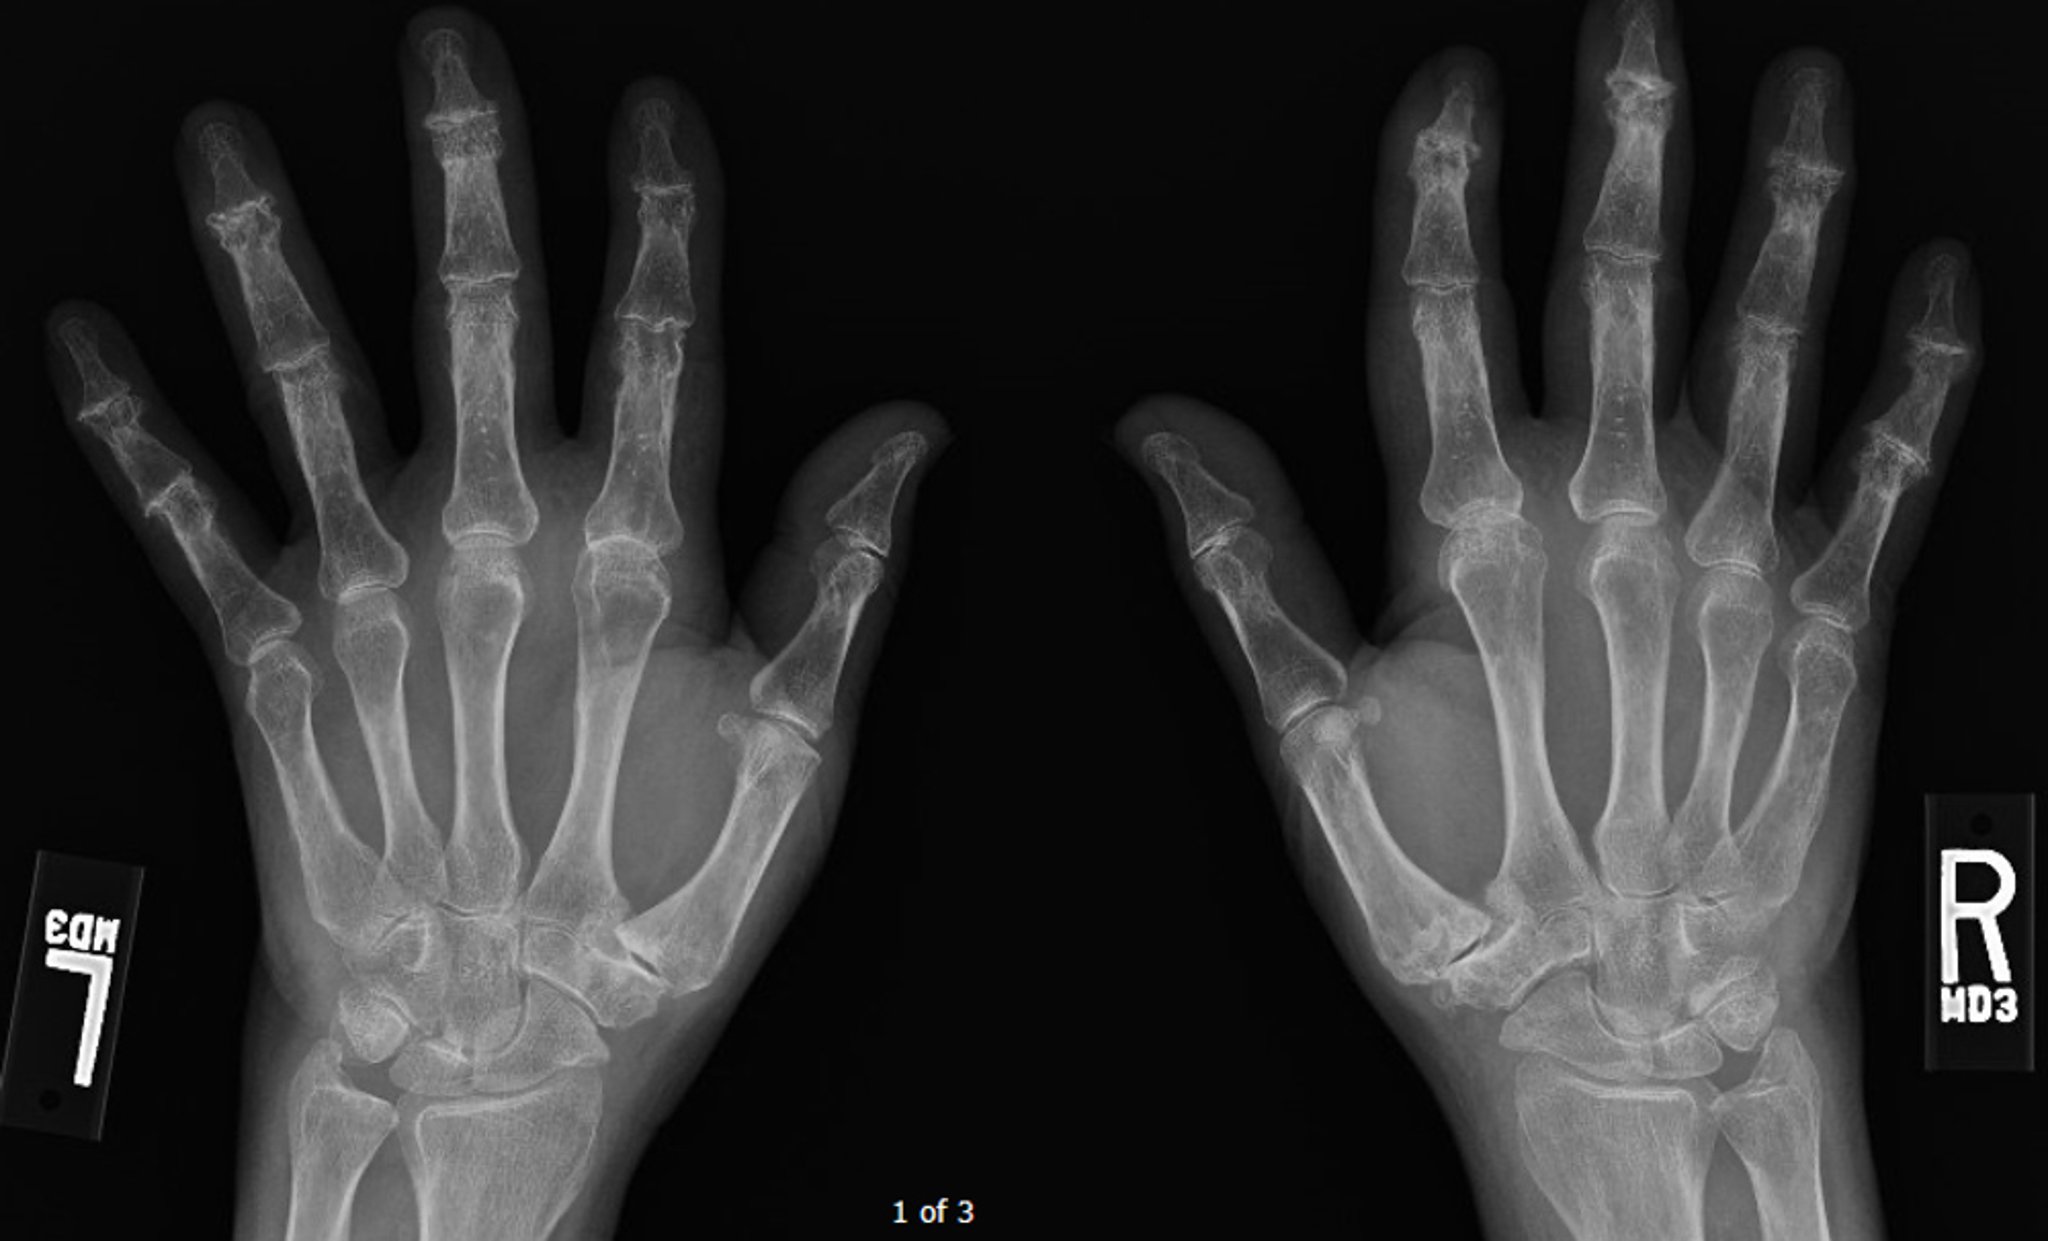

This radiograph shows advanced diffuse osteoarthritis, most prominently at the distal interphalangeal joints, where some central erosions can be seen.

Image courtesy of Kinanah Yaseen, MD.